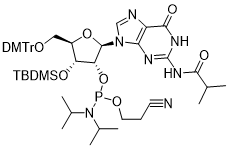

馬鞍山致研生物醫(yī)藥科技有限公司成立于馬鞍山市鄭浦港新區(qū)現(xiàn)代產(chǎn)業(yè)園。公司專(zhuān)注于生物小分子、醫(yī)藥中間體相關(guān)產(chǎn)品的研發(fā)和生產(chǎn),產(chǎn)品主要包括DNA亞磷酰胺單體、RNA亞磷酰胺單體、特殊單體以及按照客戶(hù)要求定制的RNA和DNA,并且公司提供定制合成等方面的研究服...

馬鞍山致研生物醫(yī)藥科技有限公司成立于馬鞍山市鄭浦港新區(qū)現(xiàn)代產(chǎn)業(yè)園。公司專(zhuān)注于生物小分子、醫(yī)藥中間體相關(guān)產(chǎn)品的研發(fā)和生產(chǎn),產(chǎn)品主要包括DNA亞磷酰胺單體、RNA亞磷酰胺單體、特殊單體以及按照客戶(hù)要求定制的RNA和DNA,并且公司提供定制合成等方面的研究服...